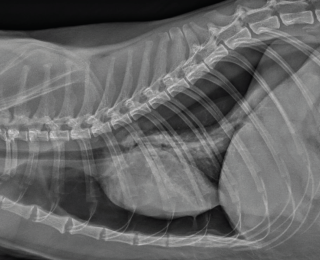

Many causes of dyspnoea are possible, and localisation is key in determining the required intervention. Thoracic trauma is common in these patients, even when there are no other visible injuries. Respiratory rate alone should not be used to exclude significant thoracic trauma and ideally survey radiographs should be performed in all patients (Figures 1 and 2) (Sigrist 2004). Table 1 gives some possible physical examination abnormalities with differentials and suggestions for diagnostics.